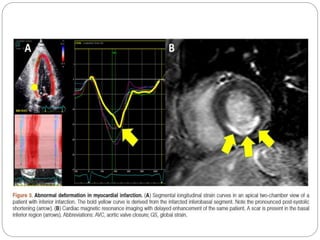

 POST SYSTOLIC SHORTENING- segment continues

shortening after the aortic valve closure( AVC), often

after a short relaxation giving one or two peaks a

systolic and a post systolic, or a single peak after AVC .

Pattern of post-systolic shortening occurring after aortic

valve closure (AVC) during coronary occlusion and

reperfusion in a patient with coronary disease